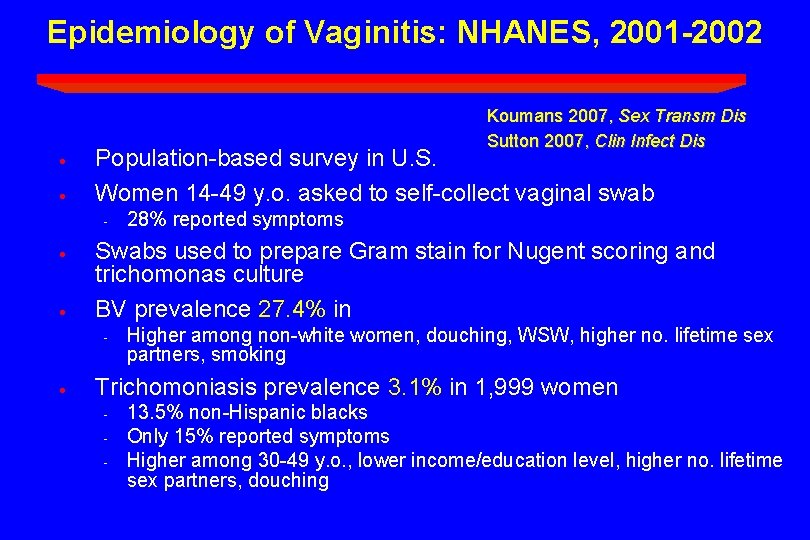

Epidemiology of Vaginitis: NHANES, 2001 -2002 · · Koumans 2007, Sex Transm Dis Sutton 2007, Clin Infect Dis Population-based survey in U. S. Women 14 -49 y. o. asked to self-collect vaginal swab - · · Swabs used to prepare Gram stain for Nugent scoring and trichomonas culture BV prevalence 27. 4% in - · 28% reported symptoms Higher among non-white women, douching, WSW, higher no. lifetime sex partners, smoking Trichomoniasis prevalence 3. 1% in 1, 999 women - 13. 5% non-Hispanic blacks Only 15% reported symptoms Higher among 30 -49 y. o. , lower income/education level, higher no. lifetime sex partners, douching